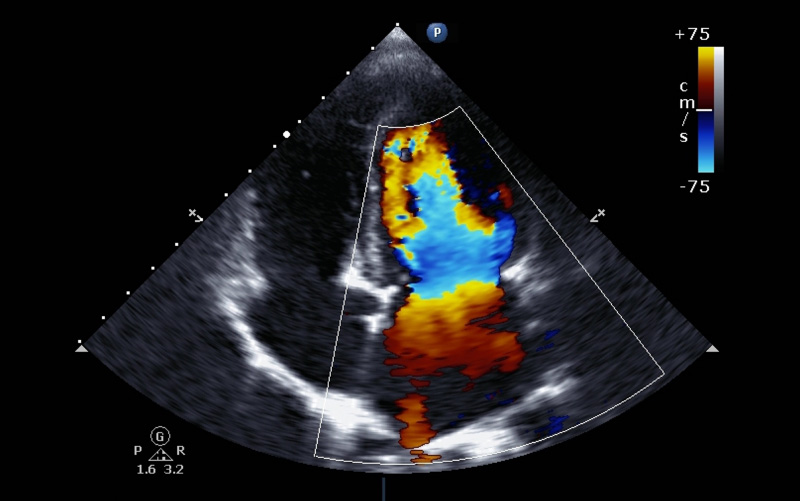

Using technology behind facial recognition programs, researchers found a way for computers to identify key elements of assessing echocardiograms.